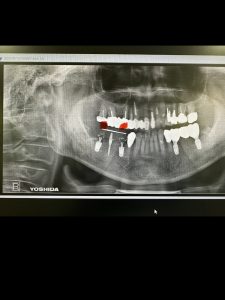

本日は右下オペ

患者さんは、4本目

左は6wで生着し既にファイナル済み

今回は暫間インプラントも併用し、バッチリ💪

ドリリングはフリーハンド

CT精査し3D画像にて方向を入念に頭に入れてれば